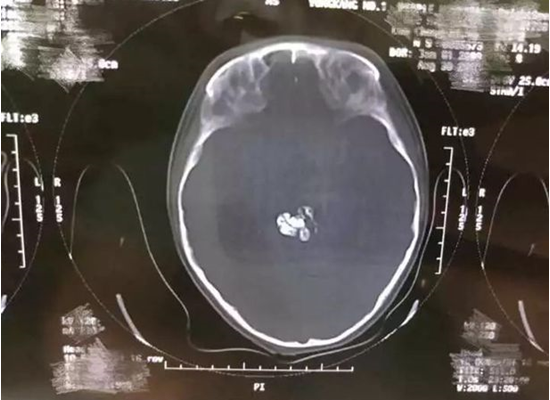

في حالة طبية غريبة تُعد الأولى من نوعها، عثر أطباء من مستشفى الأطفال في جامعة تشجيانغ الطبية، شرق الصين، على 9 أسنان تنمو داخل دماغ طفل يبلغ من العمر 5 أعوام.

وذكرت صحيفة “ميرور” البريطانية، اليوم الأربعاء، أن الطبيب “شن زهيبنج” من الجامعة الطبية الصينية، نجح في إزالة الأسنان، في عملية جراحية معقدة استمرت 6 ساعات.

وأوضح زهيبنج أن حالة الطفل ناجمة عن ورم نادر لم يكتشف منذ ولادته، حيث شكل هياكل عظمية من الأسنان داخل دماغه.